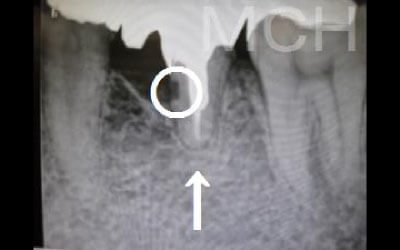

CTでは骨や歯の状態などを3次元で見ることができ、正確な距離を測ることも可能です。

骨の厚みや傾き、神経の位置などを事前にしっかり計測することで安全なインプラントが可能となります。

2 神経を傷つけるリスク

顎の骨の中を通っている神経を傷つけるリスクがあります。

ただ、事前にしっかりCT撮影して三次元的に神経までの距離を計測して治療計画を立てれば心配することはありません。

また削りすぎないためのストッパーも当院では使用しております。

骨が薄い場合は、そのままインプラントすることはお勧めできません。

ただ、事前に骨を増やす治療をしたり、インプラントと同時に骨を増やす治療をしたりすればインプラントをすることは可能です。